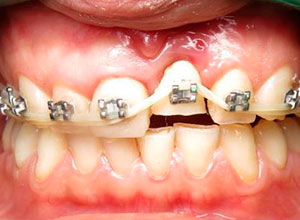

Paciente femenino a la cual le colocaron implante alto verticalmente, presentando a la vista una corona con un excedente de aproximadamente 5 milímetros, de porcelana rosa.

La paciente inconforme con los resultados nos visita, realizamos estudios radiográficos y tomográficos, encontrando que se perdió hueso verticalmente en el implante.

Decidimos hacer una corticotomia alveolar, dejando tejidos blandos en su lugar y cambiar la corona de cerámica por una corona de acrílico para cementar bien los brackets y poder empezar con la distracción.

Después de la corticotomia dejamos un tiempo de siete días para que se organizaran las células tisulares.

Se empezó a hacer la distracción, primero con un arco recto y posteriormente con elásticos haciendo el recorte con el borde incisal conforme se va bajando el implante con el bloque óseo.